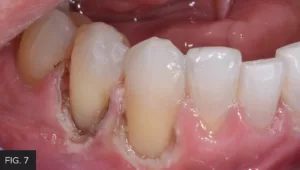

The preparation was then etched with 37% phosphoric acid, rinsed then lightly dried. G5™ All-Purpose Desensitizer (Clinician’s Choice) was scrubbed into the preparation to prevent post-op sensitivity, with the excess G5 blotted with a micro brush. A bonding agent was applied, thinned, and then light-cured with the Valo™ Grand (Ultradent™ Products, Inc.). Flowable composite was heated in the Calset™ Composite Warmer (AdDent) and placed along the cervical aspect of the preparation and light-cured, to establish a gap-free marginal seal. Additional flowable composite was then spread coronally to ensure thorough coverage of the cementum. This was followed by heated microfill composite, placed in increments and then using a REJ #04 (Clinician’s Choice) to completely fill the preparation. Care was taken before to smooth the composite as much as possible and remove excess before light-curing in order to minimize the amount of finishing time required. (FIG. 7)